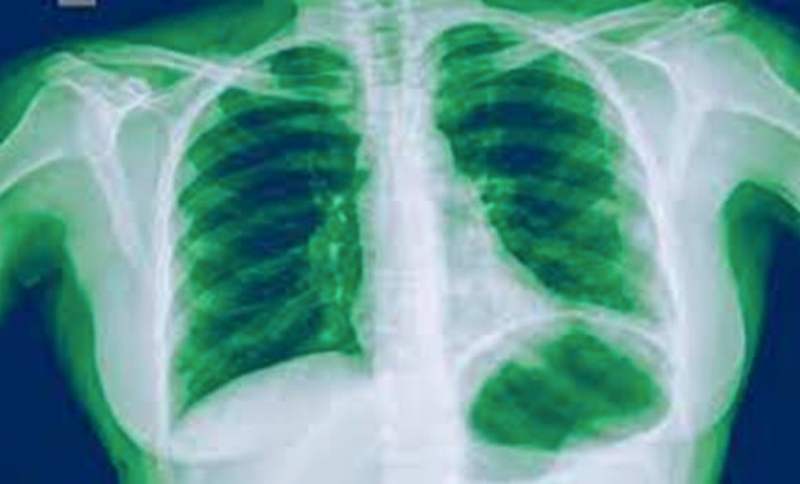

Die Lungenentzündung (Pneumonie) ist eine ernsthafte Erkrankung, die die Lungen befällt und verschiedene Ursachen haben kann. Obwohl es sich häufig um eine durch Bakterien, Viren oder Pilze verursachte Infektion handelt, kann sie auch durch schädliche physikalische oder chemische Stoffe entstehen. Diese Erkrankung kann einen gefährlichen Verlauf nehmen, besonders bei Kindern, älteren Menschen und Personen mit geschwächtem Immunsystem.

Was ist eine Lungenentzündung?

Eine Lungenentzündung ist eine entzündliche Erkrankung des Lungengewebes, die unterschiedlich stark ausgeprägt sein kann. Die Symptome können von mild bis sehr schwer reichen und in manchen Fällen eine Hospitalisierung erforderlich machen. Eine bakterielle Pneumonie, am häufigsten verursacht durch die Bakterien Streptococcus pneumoniae, Haemophilus influenzae und Staphylococcus aureus, ist ein häufiger Auslöser dieser Erkrankung. Lungenentzündungen können jedoch auch durch Viren verursacht werden, die etwa die Hälfte der Fälle ausmachen.